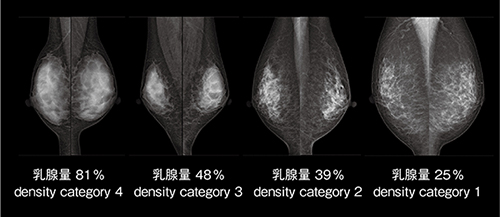

本機能は,乳腺の体積のほかに,大胸筋を除いた乳房全体の体積も算出することから,乳腺の乳房体積に対する割合,その割合に応じ分類設定を提示することが可能となります(図1)。

図1 乳腺量とカテゴリー分類